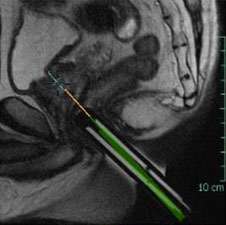

LEFT: Oblique Axial T2-weighted image from in-bore MR-guided targeting

RIGHT: Corresponding sagittal T2-weighted image from in-bore MR-guided targeting